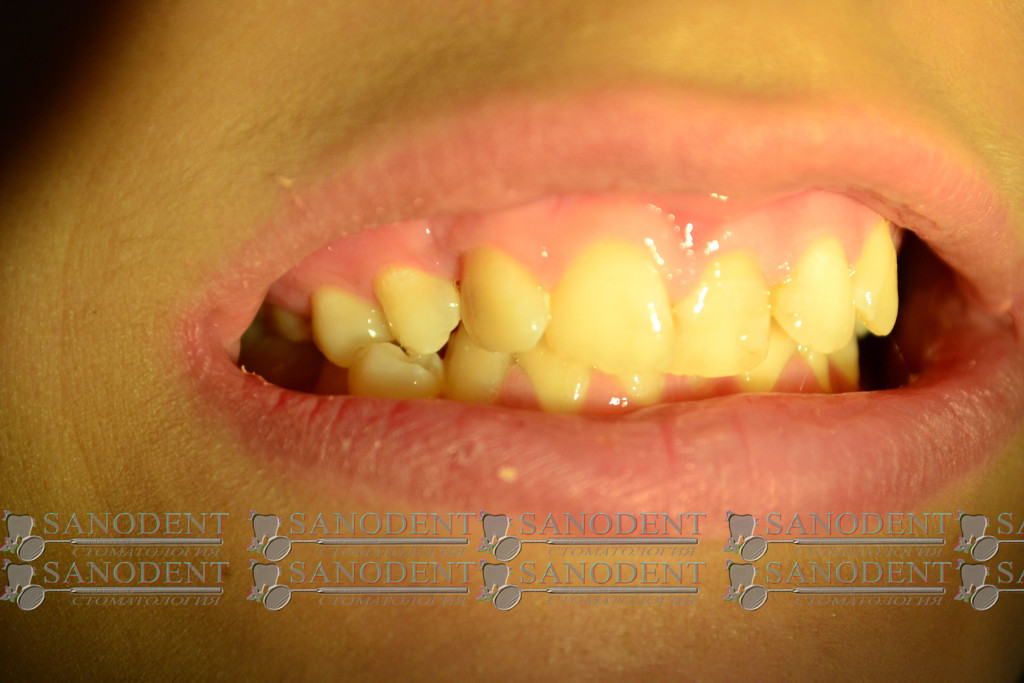

Довольно сложная работа по протезированию ввиду неправильного прикуса пациента и категорического отказа проходить ортодонтическое лечение. Проводилось формирование правильного прилегания коронок к десне . Улучшение эстетики улыбки с помощью керамических виниров.

- до лечения

- искривление зубного ряда

- многочисленные дефекты эмали